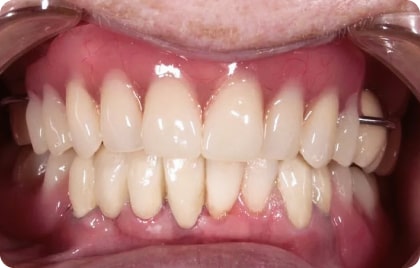

Зубы за 1 день от 7500₽ в месяц

с пожизненной гарантией

Установка

за 1 день